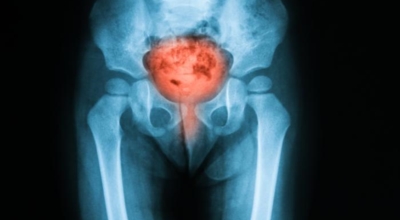

방광염 증상 - 혈뇨

소변을 볼때 화끈거림이 있다면서 피가 섞여 나오기도 합니다. 소아 방광염 증상의 경우 배의 통증, 38C 이상의 고온, 약점 및 과민 반응, 식욕 감소 또는 토악질와 같은 증상이 나타날 수 있어요.